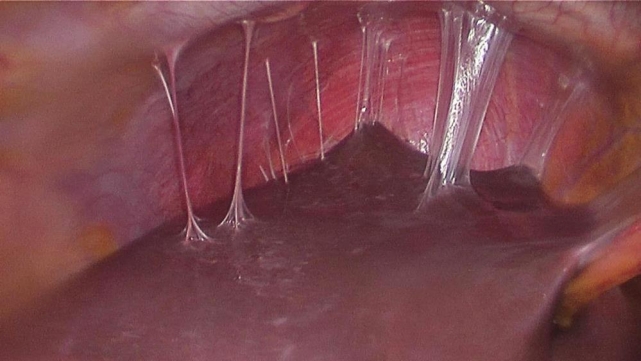

Fıtık onarımının dünya çapında en yaygın cerrahi prosedürlerin başında geldiğine işaret eden Prof. Dr. Esra Karaca, her yıl yaklaşık 20 milyon hastanın fıtık gelişimine bağlı olarak ameliyat edildiğini açıkladı. Karın duvarında oluşan defektin, mesh adı verilen bir tıbbi tekstil materyali implante edilerek onarılmasının da bu alanda yapılan en yaygın cerrahi müdahalelerden birisi olduğunu söyleyen Prof. Dr. Esra Karaca, “Bununla beraber, kullanılan meshler ciddi adezyonlara neden olmaktadır. Daha önce fıtık ameliyatı olmuş hastaların yüzde 90'ından fazlasının ameliyat sonrası adezyon semptomları gösterdiği tespit edilmiştir. Adezyonlar ise kronik karın ağrılarına ve iç organlarda ölümcül tıkanıklıklara yol açabilmektedir. Yeni ürünler denenmesine rağmen, post-operatif adezyon henüz başarıyla önlenememiştir. BUÜ Tıp Fakültesi Hastanesi’nden Türkiye ile ilgili bir projeksiyon yapılarak, ülkemizde bir yılda kullanılan fıtık mesh sayısının 100 bin civarında olduğu sonucuna varılmıştır. Bu nedenle; proje çerçevesinde geliştirilecek başarılı bir kompozit meshin, yurt dışından mesh ithalatını önemli oranda azaltacağı öngörülmektedir” açıklamasında bulundu.

Karaca ayrıca projede, karın fıtıklarının onarımında kullanılmak üzere çörek otu yağı içeren anti-adezyon özellikli nanolifli yüzey ile takviyelendirilmiş PP örme mesh yapıların geliştirilmesi ve kompozit meshlerin fıtık onarımı ve adezyon önleme performansının in vitro ve in vivo çalışmalarıyla değerlendirilmesini hedeflediklerini de sözlerine ekledi.